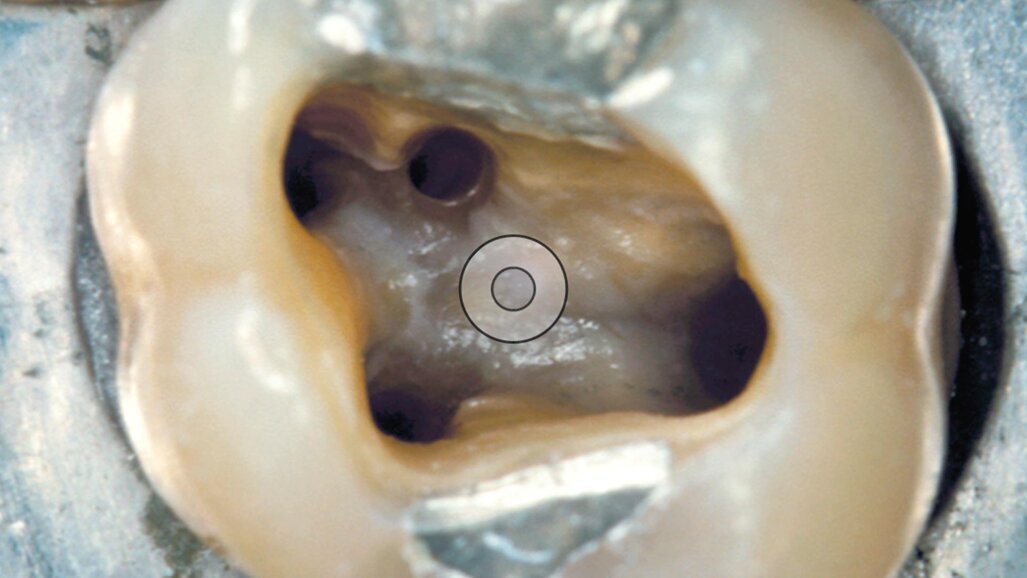

Questa punta è stata disegnata per rifinire la cavità d’accesso dei premolari e dei molari (Figg. 5, 6). Ha forma troncoconica. La parte lavorante è lunga 12 mm, la punta ha un diametro di 0,8 mm, il diametro massimo dell’inserto alla fine della parte lavorante è di 1,6 mm. La punta dell’inserto non è attiva, possiamo quindi paragonarla ad una fresa di Batt o alla Endo Z.

Fig. 4 -La A-C Tip ED51 è disegnata per la rifinitura delle pareti della cavità d’accesso.

Fig. 5 - - La A-C Tip ED51 è disegnata per la rifinitura delle pareti della cavità d’accesso dei molari superiori e inferiori.

Fig. 6 - La A-C Tip ED51 è disegnata per la rifinitura delle pareti della cavità d’accesso dei premolari superiori e inferiori.